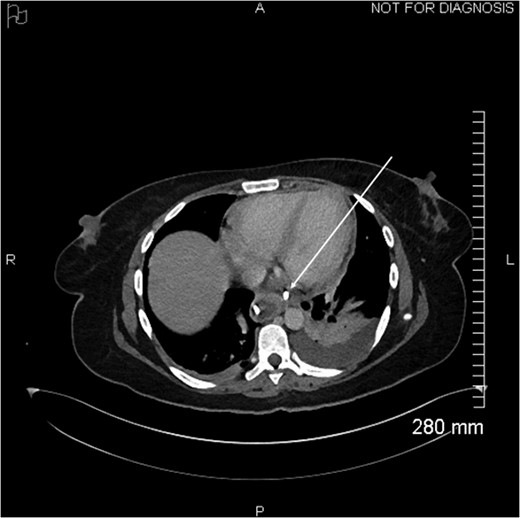

Axial view of opacification on CT showing the externalization of the drain in the pericardium (arrow).